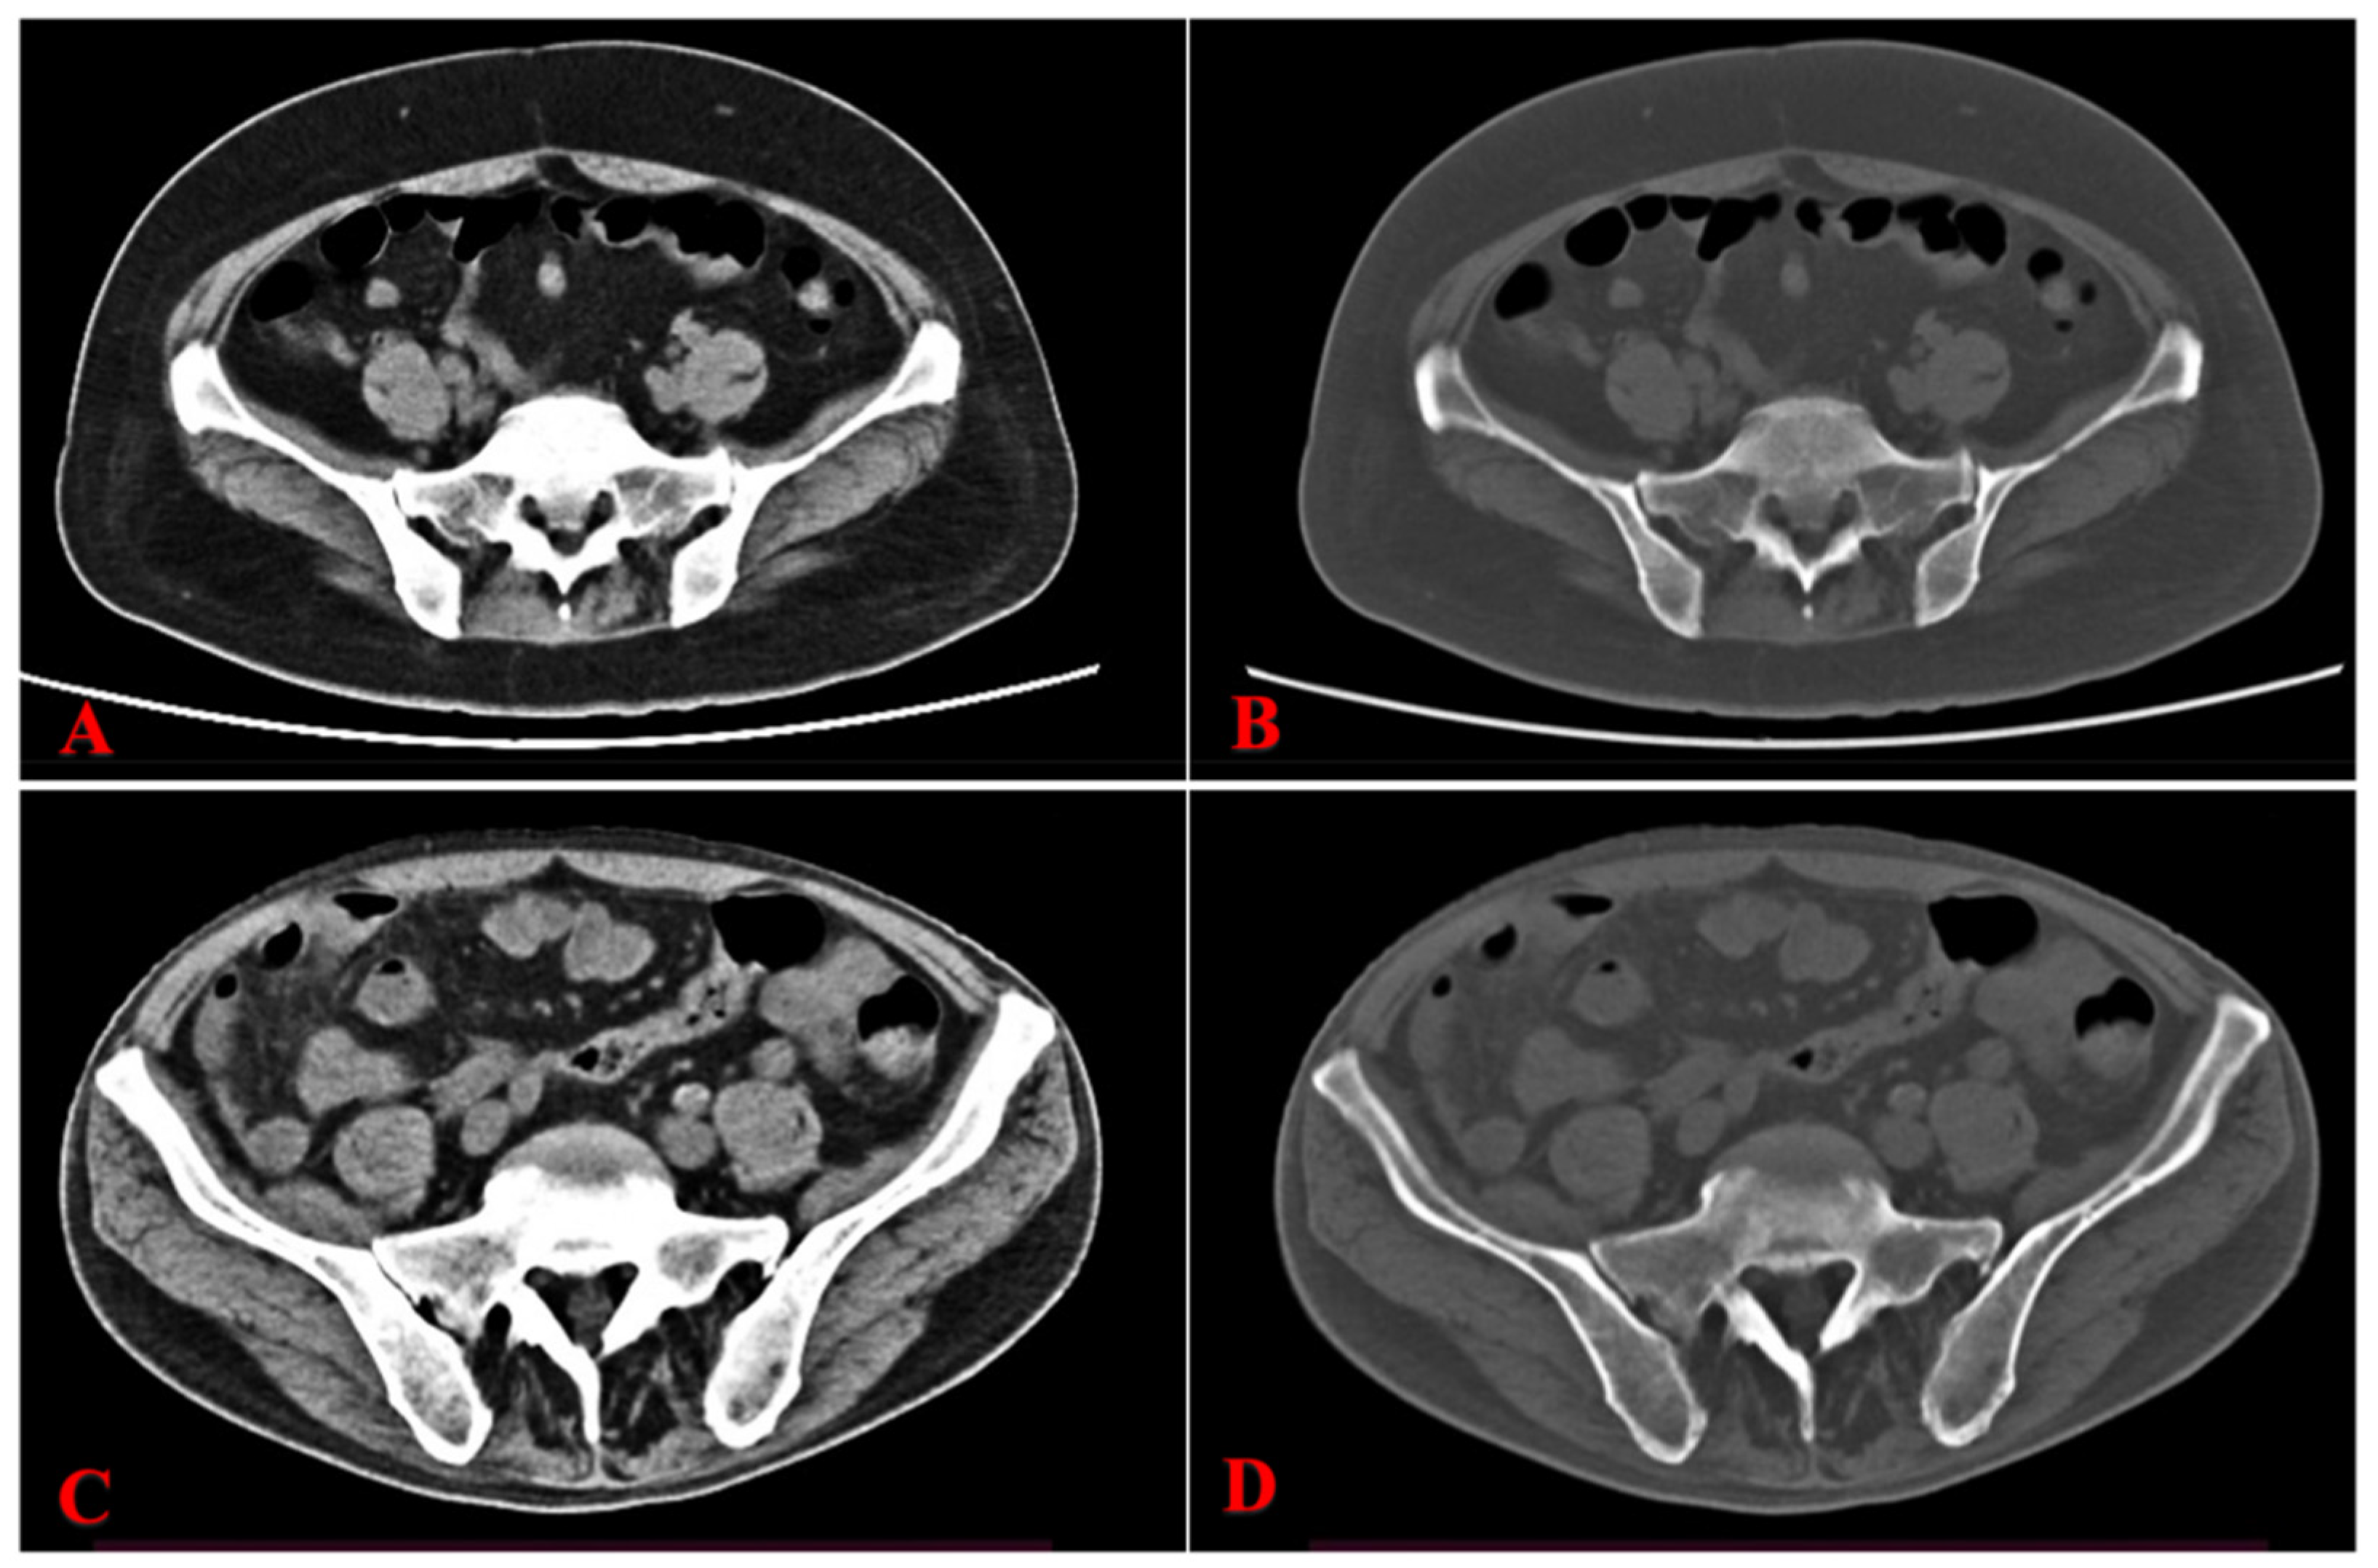

Figure 2.

Pretreatment CT images of representative AML patients who achieved complete remission (CR) and those who did not achieve complete remission (NCR). (A): Axial unenhanced CT with an abdominal window, and (B): a bone window showed an increased bone marrow density of both iliac bones (CT: 212.03 HU). (C,D): A representative AML patient who achieved NCR after the therapy. (C): Axial unenhanced CT with an abdominal window, and (D): a bone window showed a lower bone marrow density of both iliac bones (CT: 116.08 HU). AML, acute myeloid leukemia; CR, complete remission; NCR, non-CR.